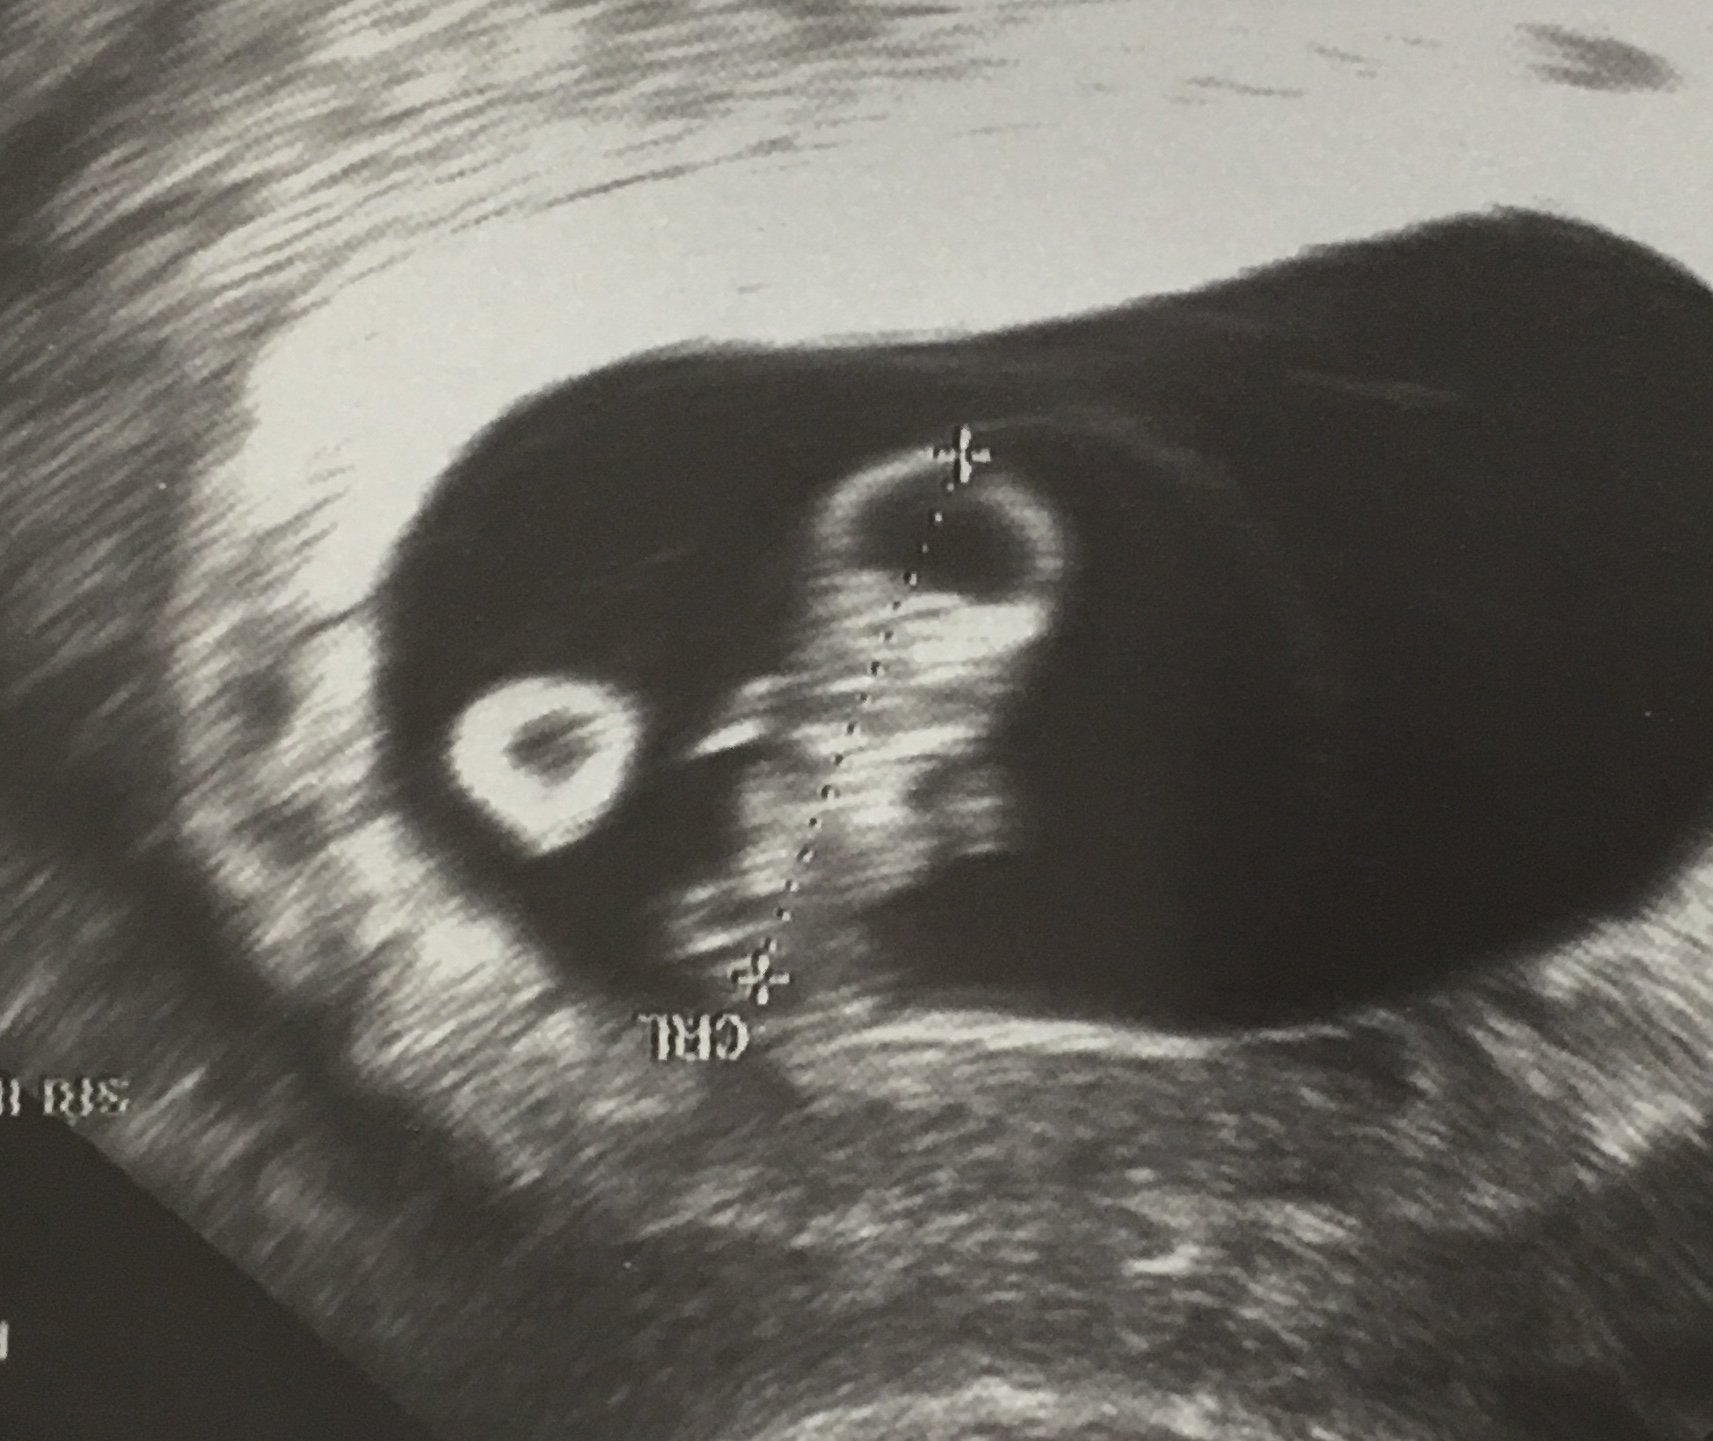

Thought I was 8 weeks yesterday turned out im 7 weeks and 4 days as of today. I have to go back in two weeks to make sure baby is okay and growing. That made me nervous but as long as I get to see her/him again and hear her/his beautiful hb I'm okay with that. Is it normal to have to go back tho? just curious